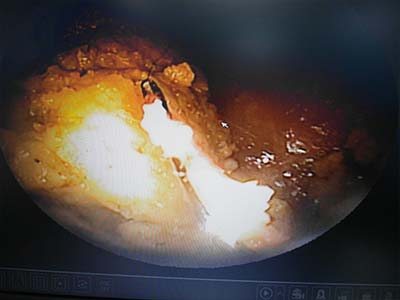

內視鏡可以看到針卡在胃部

內視鏡中看到骨頭影像

用工具夾住骨頭